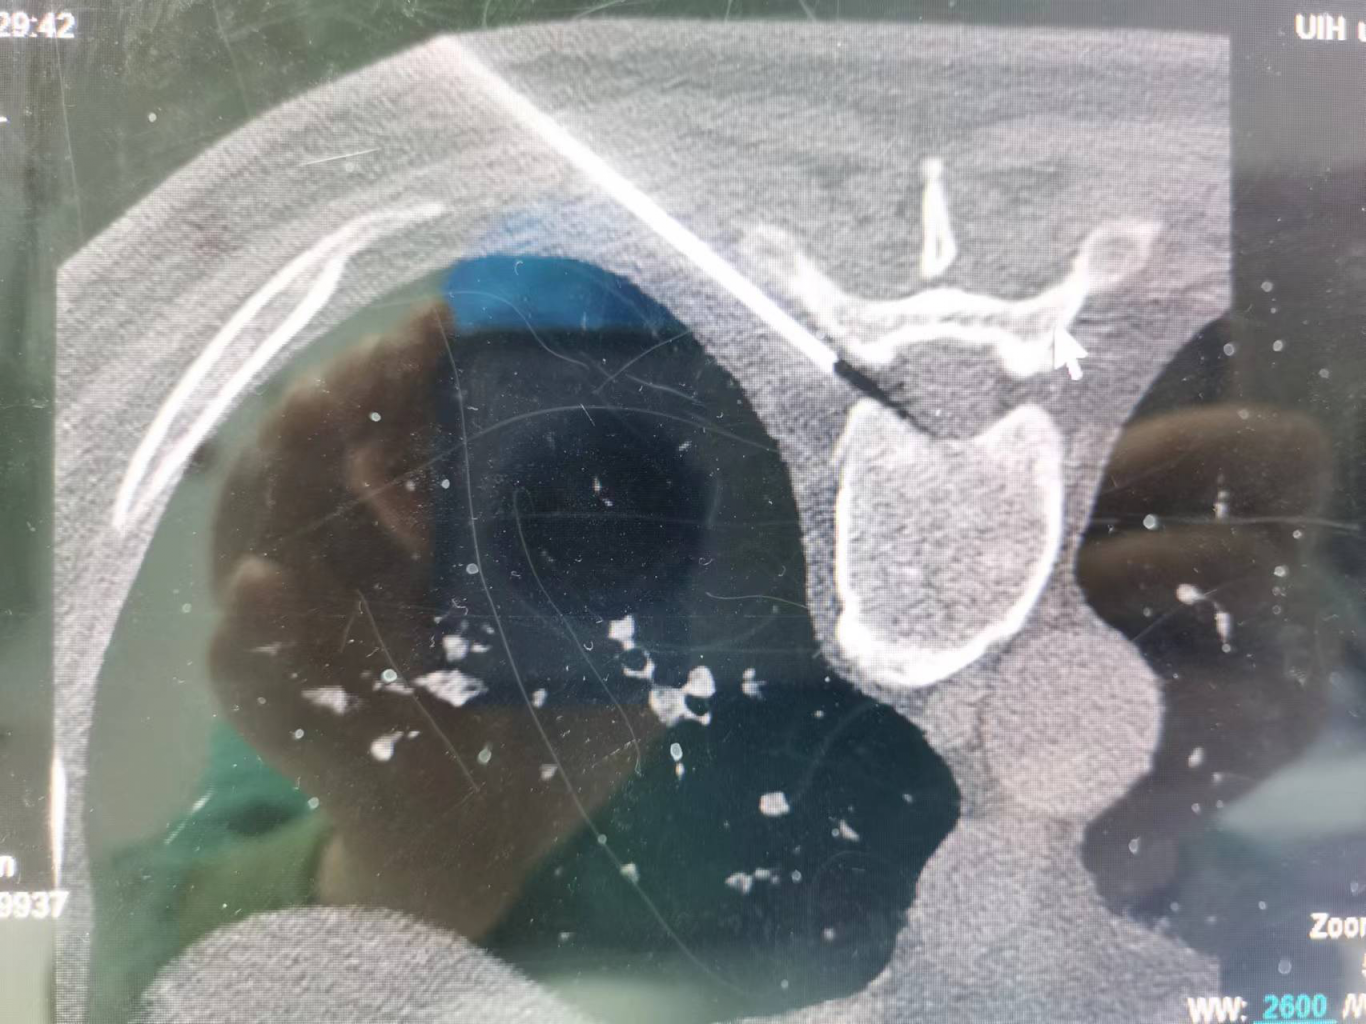

神經(jīng)調(diào)控:包括神經(jīng)射頻、電刺激等,是目前治療帶狀皰疹后神經(jīng)痛最有利的手段。通過(guò)干預(yù)神經(jīng)電信號(hào),減少疼痛傳遞,促進(jìn)鎮(zhèn)痛物質(zhì)釋放,可以達(dá)到更佳持久的鎮(zhèn)痛效果。尤其適用于后遺神經(jīng)痛的治療。